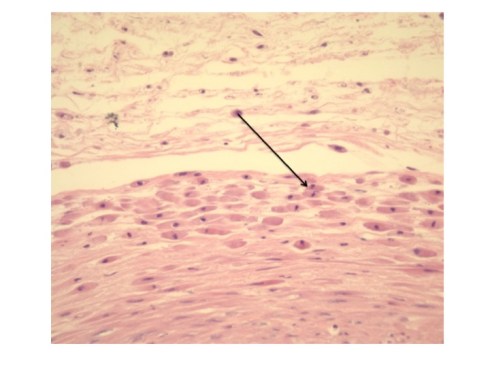

Some authors have turned the association of meconium and fetal distress around and have argued that meconium can cause fetal asphyxia by injury to umbilical cord vessels25-27. There are two types of evidence for this contention. One is the association of meconium stained umbilical cords with vascular smooth muscle necrosis in infants with neurologic injury. The “meconium induced vascular necrosis” is a very distinctive lesion with necrotic muscle cells on the outer muscle layers and toward the umbilical cord surface (Fig3). Yet, it is equally plausible that this pattern is not from diffusion of meconium inward, but from necrosis in the areas of lowest oxygen levels in the umbilical cord vessels.

Fig 3: This is from an umbilical cord with meconium macrophages at the back of the arrow and superficial smooth muscle necrosis of the outer layer of the umbilical vein(H&E, 20x)